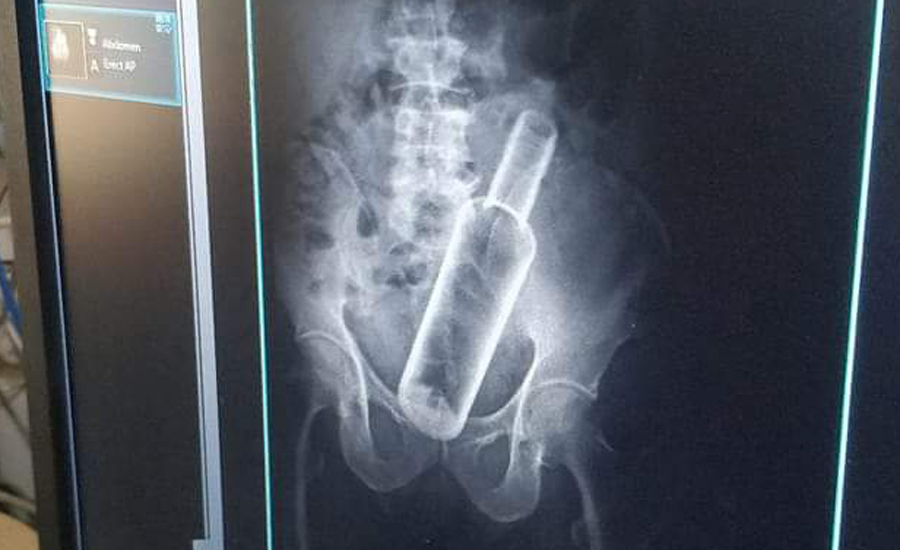

धनगढी । सेती प्रादेशिक अस्पतालमा उपचार गर्न गएका एक वृद्धको पेटमा बोतल भेटिएको छ । धनगढीको फूलबारी बस्ने ६१ वर्षीय जमनसिंह रोकामगरको एक्सरे गर्दा पेटमा रक्सीको बोतल देखिएको अस्पतालले जनाएको छ ।

प्रादेशिक अस्पतालका सूचना अधिकारी मेखराज उपाध्यक्षले दिएको जानकारी अनुसार बिहीबार पेट दुखेपछि अस्पताल आएका रोकामगरको एक्सरे गर्ने क्रममा बोतल देखिएको हो ।

उनकाअनुसार केही दिनअघि मदिरा सेवन गर्ने क्रममा साथीले मलद्वारबाट बोतल पेटमा घुसाइदिएको बताएका छन् । उनको प्रादेशिक अस्पतालमा उपचार भइरहेको छ ।